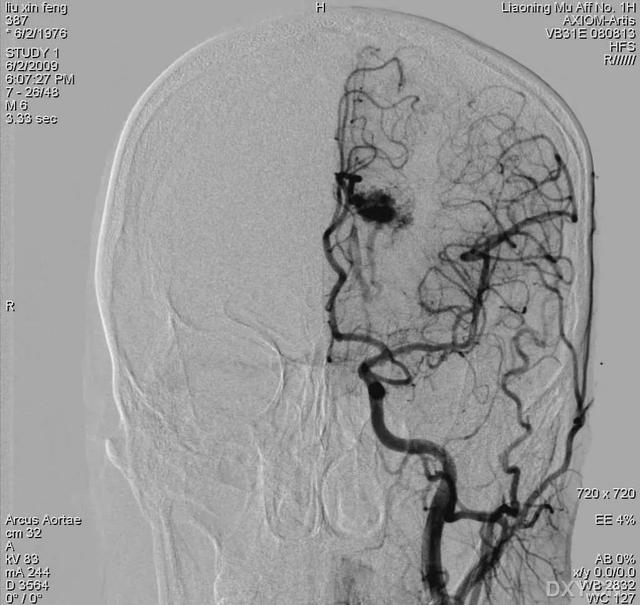

中老年人可以进行头部CT、颈部血管彩超,经颅多普勒,磁共振等设备的检查,可以评判颅内血管的状态。